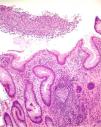

Nine patients with anorectal involvement underwent rectosigmoidoscopy, which revealed extensive superficial ulcers with geographic borders in the anal canal and rectal ampulla (Fig. 4). The main histopathology findings were granulomatous patterns with nonspecific chronic infiltrates associated with acute cryptitis in 3 cases (Fig. 5). No microorganisms were observed in the biopsy, and immunohistochemistry for cytomegalovirus and Treponema pallidum was negative. Patient 1 underwent magnetic resonance imaging, which revealed edema of the rectal mucosa with obliteration of the lumen extending into the mesorectal fat associated with multiple enlarged pararectal and hypogastric lymph nodes. In patients with classic LGV, ultrasound proved useful for demonstration and follow-up of the enlarged inguinal lymph nodes, abscesses, and fistulas. Serovar L2 of C trachomatis (GenBank reference CP002682.1) was identified as the etiologic agent in all cases.